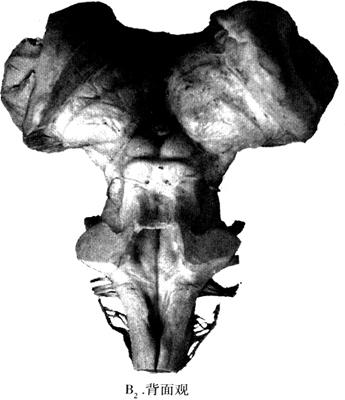

图12-26 脑干的外形(B2)

在脑干背侧面,各部分界线不如腹面明显(图12-26B)。在延髓与脑桥背面可见菱形窝(rhomboid fossa)和中脑背侧的上丘(superior colliculus)、下丘(inferiorcolliculus),以及位于下丘下方的唯一由脑干背侧出脑的Ⅳ对脑神经(trochlear nerve),菱形窝的髓纹可作为延髓与脑桥在背侧的分界线。

菱形窝的第四脑室底,其表面有如图12-26B所示的隆起(如内侧隆起(medial eminence))、丘(如面神经丘(facial colliculus))或三角(如迷走神经三角(vagal trigrne)),其深面有(图12-27、图12-28)所示脑神经核。为便于记忆将菱形窝脑神经核分布概况于图12-29、表12-2,并将其系统化。

正中沟分菱形窝为左右两半,髓纹(striac medullares)将其分上下两半,界沟(sucus limitans)再把一侧的菱形窝分成内侧和外侧两份。界沟内侧份髓纹上方为内侧隆起(medial eminence)和面丘(facial colliculus),后者深面有展神经核(abducens nucleus)。髓纹下方有舌下神经三角(hypoglossal triangic)和迷走神经三角(vagal triangle),二者的深面分别藏有舌下神经核(hypogolossal nucleus)和迷走背核(dorsal nucleus of vagus nerve)。界沟外侧,均为前庭区,内有前庭神经核和外侧的蜗神经核(cochlear nucleus)。